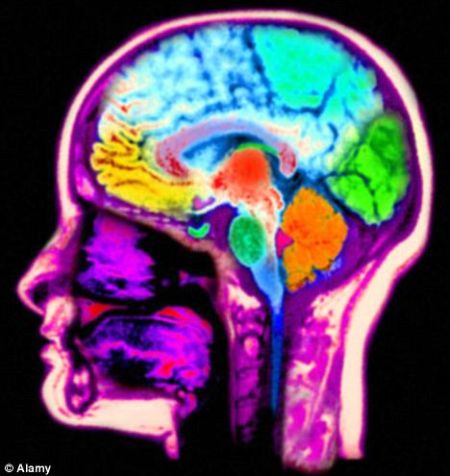

据一项最新研究称,人类大脑只有860亿个神经元

狒狒也拥有大约860亿个神经元

新浪科技讯 北京时间3月5日消息,据国外媒体报道,神经科学界一直的共识是,人类大脑包含1000亿个神经元。但是最新研究称,这一数字其实比实际多了140亿个。

据巴西神经学家苏扎娜-赫尔库拉诺-霍泽尔说,事实上人类与狒狒拥有相同数量的神经元,都是860亿。她在同事的帮助下,以一种相当恐怖的方式——把4颗大脑加工成“大脑汤”,然后计算神经元的细胞核数,确定人类大脑包含神经元的真实数量。这些大脑属于4名年龄分别是50岁、51岁、54岁和71岁的成年男性,他们捐献大脑用于科学研究,其中没有一人患有神经系统疾病。

赫尔库拉诺-霍泽尔博士说:“我们发现平均一个人类大脑拥有860亿个神经元。迄今为止我们观察的大脑,没有一个的神经元数量是1000亿。尽管这听起来可能只是一个很小的差额,但是140亿在狒狒的大脑所拥有的神经元数量中仍占很大比例,或者几乎相当于大猩猩大脑的神经元数的一半。因此这其实是一个很大的差额。”这一数字令人大吃一惊,因为大部分有关神经元的教科书和文章都赞成人类大脑拥有1000亿个神经元的观点。然而赫尔库拉诺-霍泽尔的研究并未发现这么多神经元。

她的研究象征着神经系统学向前迈进的一大步,但这只是在她制作“大脑汤”后得出的。她说:“我花了几个月时间,才打定主意要把一些人的大脑或者动物大脑制成汤状物。不过我们早就了解到,通过这种方法可以得到人们一般无法得到的数字。这种方法并不比把一个大脑切成碎片更糟糕。”尽管她的研究结果意味着我们的智力并没那么高,但是与其他灵长动物相比,我们仍很聪明,因为我们有更多神经元是致力于认知和行为的。(新浪科技 秋凌)